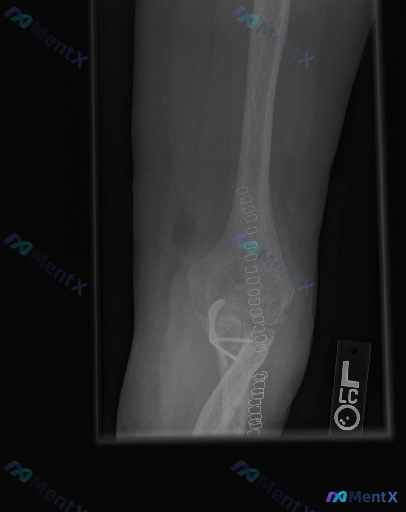

整理了一份肘关节术后的侧位X光影像分析资料,先不直接给结论,大家一起来看看读片思路。 影像基本情况 - 标记为左侧(L)肘关节侧位片 - 可见肱骨远端、尺骨近端的金属内固定系统(钢板、螺钉),还有串珠状高密度缝合钉影 - 术区有金属伪影干扰 - 局部可见骨密度增高区域(考虑骨痂形成迹象) - 目前未...